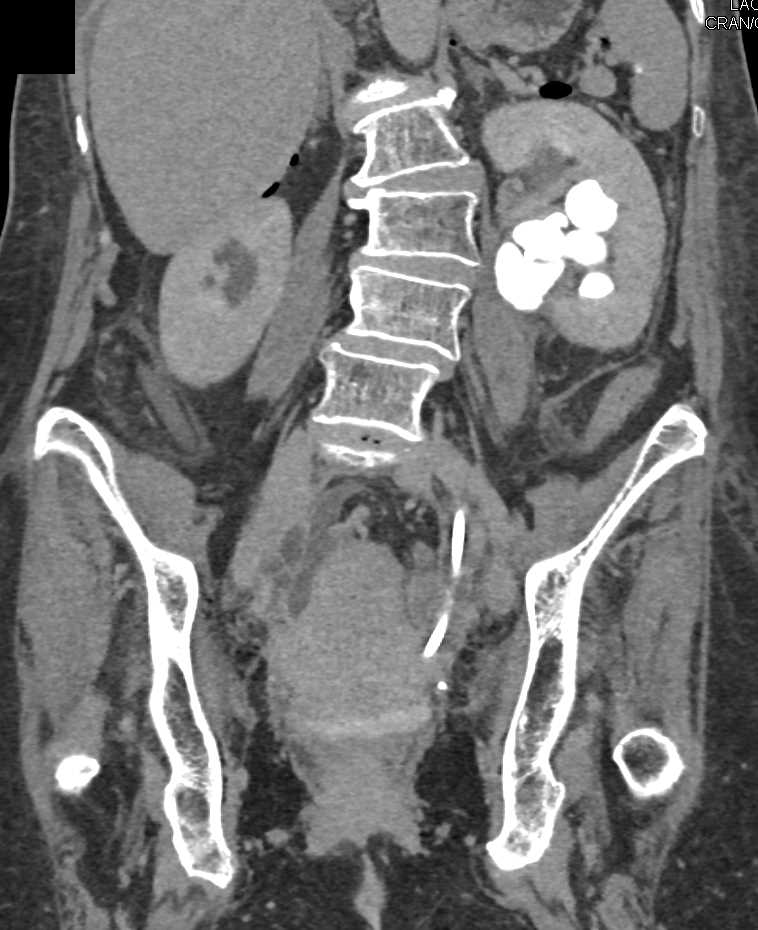

Cystic Left Renal Cell Carcinoma